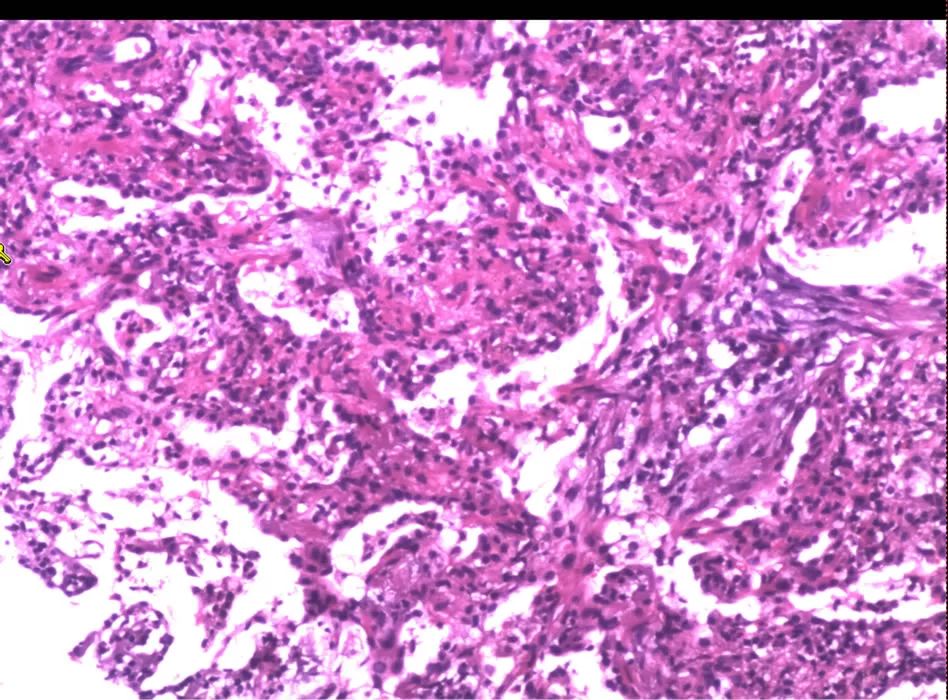

支气管肺活检:肺泡和间质嗜酸性粒、淋巴细胞堆积,间质 轻度纤维化